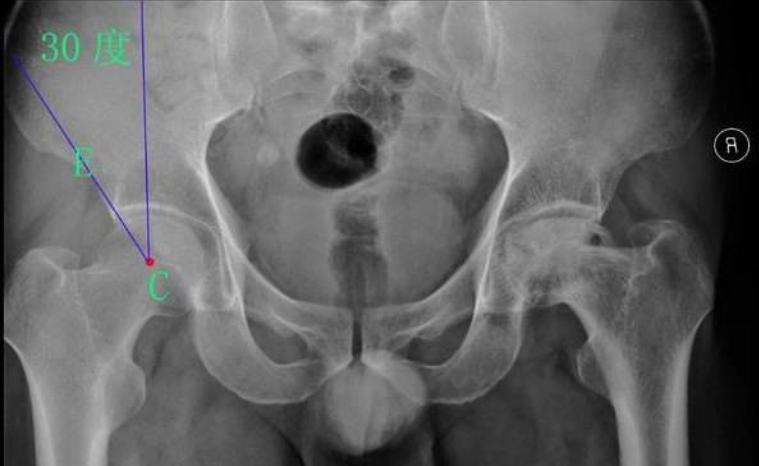

在正位X线片上,髋白发育不良主要表现为髋白发育浅小或浅平,股骨头的负重侧间隙增宽,并继发骨性关节炎。髋关节正位、蛙位X线片是了解与判断髋关节发育不良程度的最基础的影像学检查。